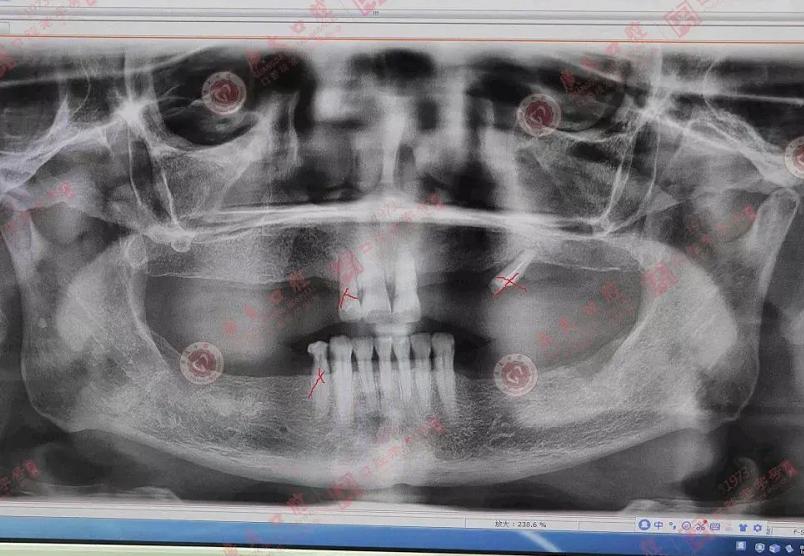

术前牙片

术前检查